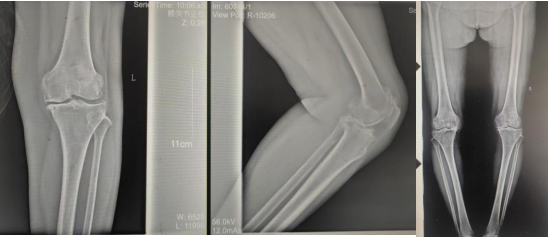

術(shù)前影像資料

張女士于10年前勞累后左膝疼痛,干活后疼痛較重,陰雨天及受涼時(shí)疼痛明顯,行走時(shí)可聞及關(guān)節(jié)內(nèi)異響,時(shí)有“打軟腿”現(xiàn)象,曾到附近多家醫(yī)院診治,給予膝關(guān)節(jié)針灸、膏藥外貼、口服藥物等“保守”治療,治療后疼痛癥狀略有好轉(zhuǎn),但易復(fù)發(fā);近2年患者左膝關(guān)節(jié)疼痛逐漸加重,行走跛行,下蹲及上下樓梯困難,活動(dòng)時(shí)疼痛明顯,休息、保守治療后疼痛無(wú)明顯好轉(zhuǎn)。

張女士的鄰居看她上下樓如此困難,日常生活都很受影響,因其以前在我院看過(guò)腰椎,效果良好,故介紹張女士來(lái)我院找萬(wàn)昌勝主治醫(yī)師進(jìn)行咨詢問(wèn)診。萬(wàn)醫(yī)生了解情況后帶她到我院關(guān)節(jié)外科進(jìn)行更專業(yè)的診治。關(guān)節(jié)外科門診醫(yī)師結(jié)合癥狀體征及影像學(xué)檢查,建議入院手術(shù)治療,以“左膝骨性關(guān)節(jié)炎伴膝內(nèi)翻、高血壓病”收住入院。